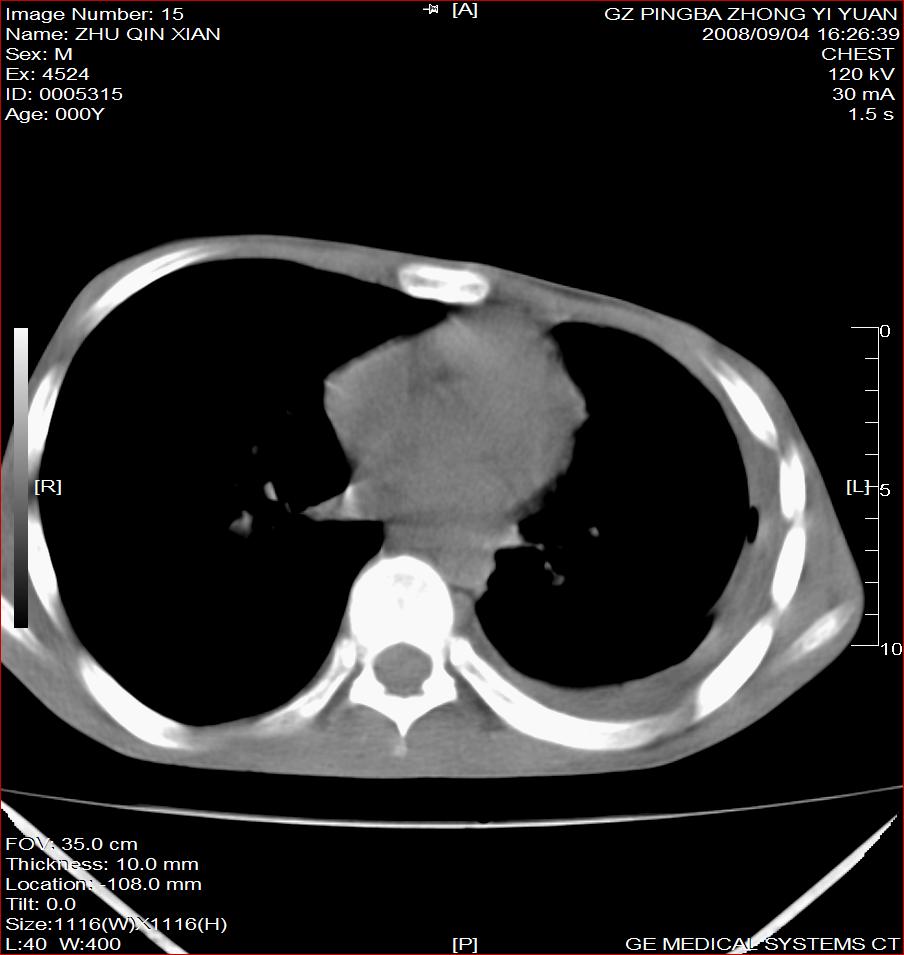

以下是引用随光逐影在2008-9-4 20:05:00的发言:[br]1)考虑两肺结核。2)左侧胸膜炎(胸膜肥厚、粘连,胸腔积液)。3)左侧局限性气胸。

以下是引用子十在2008-9-4 19:34:00的发言:[br]左上肺结核并空洞及双肺播散。节段性肺不张、胸腔积液、胸膜肥厚粘连。[br]